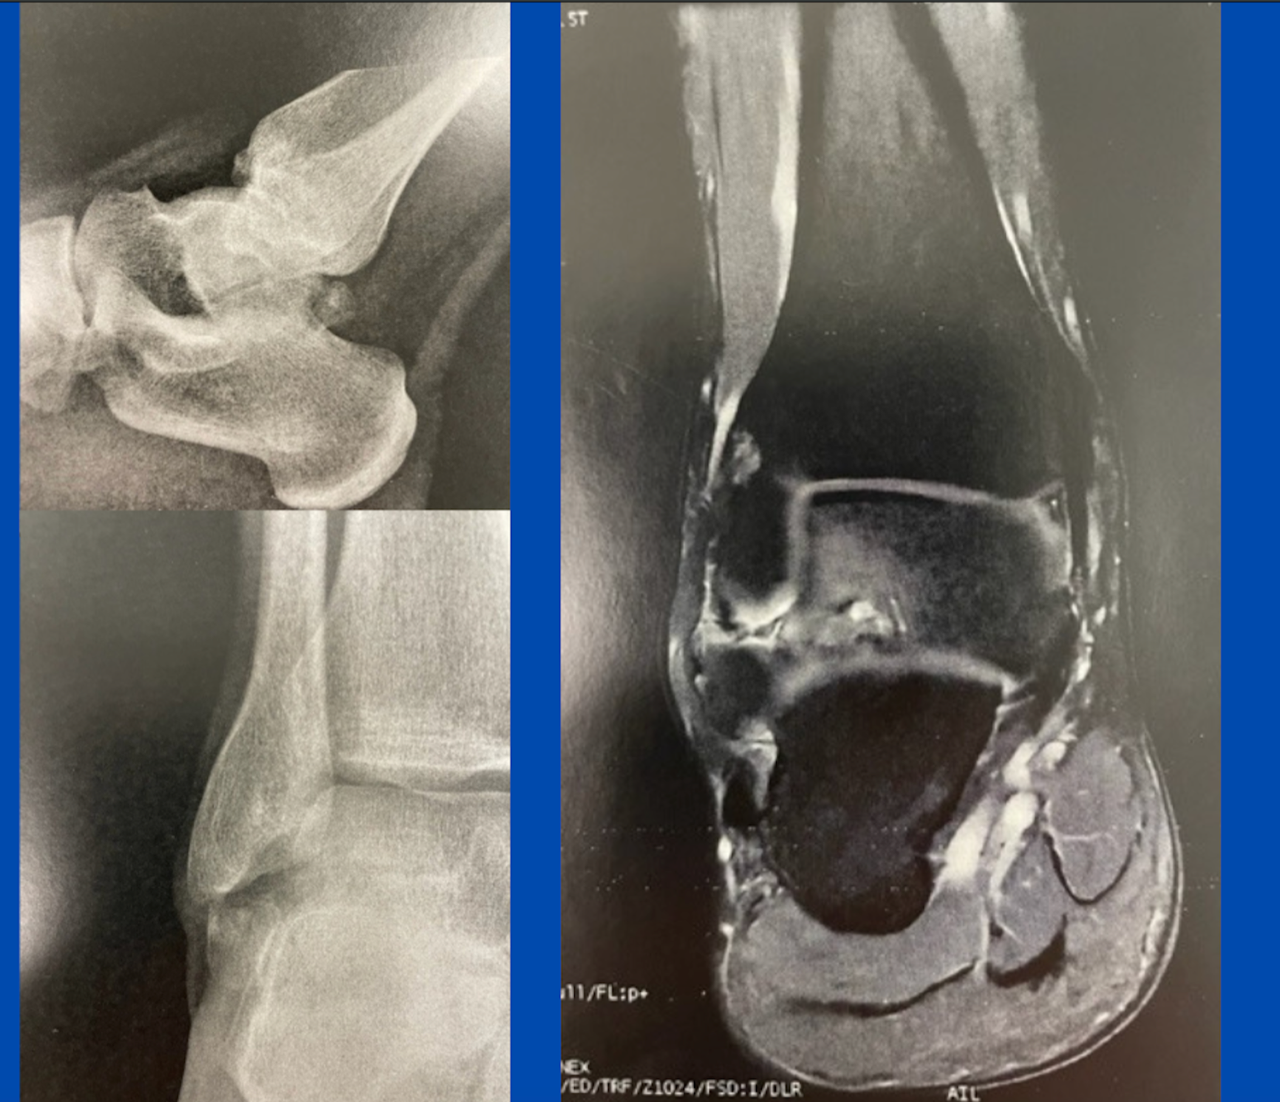

Posterior “ankle pain”

By |August 7th, 2023|

Blog's main page This active 25-year-old has presented with marked "ankle pain" following all activities. He remembers a severe inversion sprain when he was a child and informs me he [...]